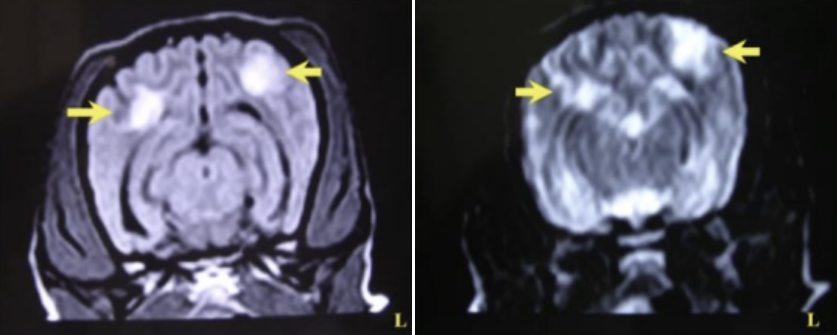

- Brain MRI ๊ฒฐ๊ณผ ์ก์์ข ์ฑ ๋์๋ง์ผ ์๊ฒฌ (์ข ์์ฒ๋ผ ๋์ ์๊ธด ํ์ ๋ถ๋ถ๋ค)

| MRI | |

![]() | ์ผ์ชฝ ๊ฐ์ชฝ๋์ค ์ ๋ณด์. ์ผ์ชฝ ๋ ์ ์ฒด์ ์ฌํ ์ผ์ฆ์ฑ ์๊ฒฌ |

![]() | ๋์ฒ์์ก ์ธ์ ๋ถ๋ถ์์๋ signal ์ฆ๊ฐ ๋๋ ์ ์ฒด์ multifocalํ ์ผ์ฆ ๋ฐ์ |

![]() (๋ชจ๋ฅด๊ฒ ๋ค๊ณ ? ๋๋ ๊ทธ๋..) | ์ผ์ชฝ์์ ๊ฐ์ชฝ๋์ค ์ ์ ๋ณด์, ์ผ์ฆ์ ์ํ edema. linearํ๊ฒ ๊ตญ์์ ์ธ ์กฐ์ ์ฆ๊ฐ โ ํ๊ด์ ์ผ์ฆ์ ์๋ฏธ * solitary, ๋ช ํํ๊ฒ ๊ตฌ๋ณ๋๋ ์กฐ์ ์ฆ๊ฐ โ ์ข ์ * linear/diffuse ํํ์ ์กฐ์ ์ฆ๊ฐ โ ํ๊ด ์ผ์ฆ |